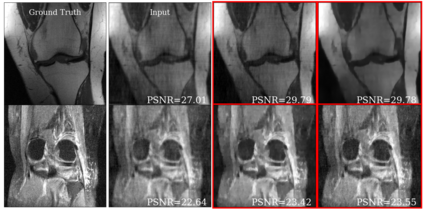

Deep learning based techniques achieve state-of-the-art results in a wide range of image reconstruction tasks like compressed sensing. These methods almost always have hyperparameters, such as the weight coefficients that balance the different terms in the optimized loss function. The typical approach is to train the model for a hyperparameter setting determined with some empirical or theoretical justification. Thus, at inference time, the model can only compute reconstructions corresponding to the pre-determined hyperparameter values. In this work, we present a hypernetwork based approach, called HyperRecon, to train reconstruction models that are agnostic to hyperparameter settings. At inference time, HyperRecon can efficiently produce diverse reconstructions, which would each correspond to different hyperparameter values. In this framework, the user is empowered to select the most useful output(s) based on their own judgement. We demonstrate our method in compressed sensing, super-resolution and denoising tasks, using two large-scale and publicly-available MRI datasets. Our code is available at https://github.com/alanqrwang/hyperrecon.